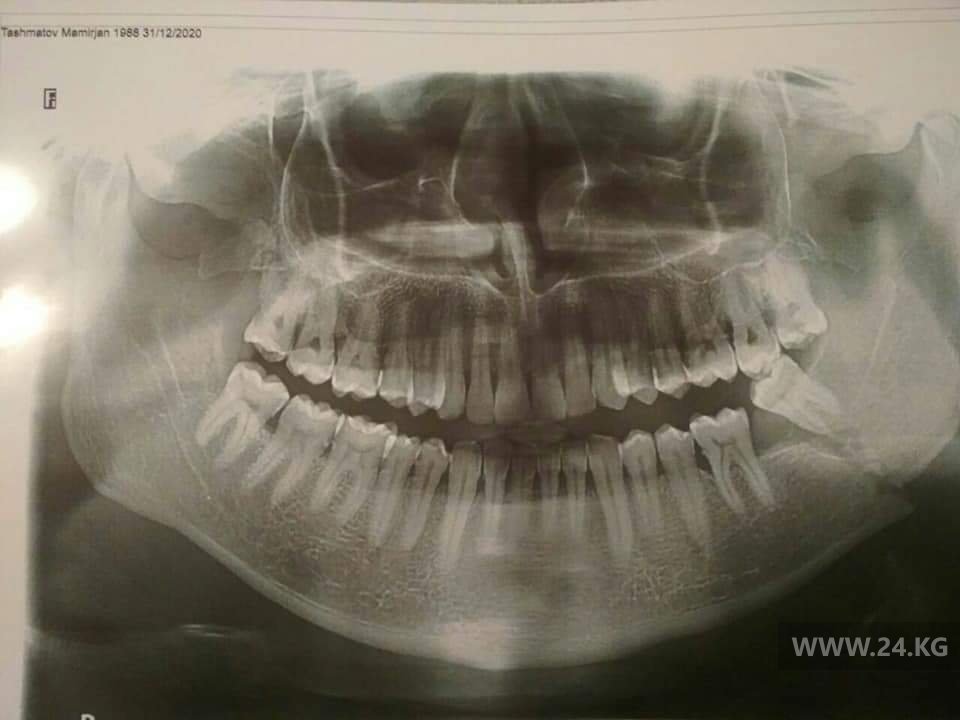

«Оказалось, что в одном из домов на этой улице спецназ проводил обыск. Я стоял, как и все, в толпе. Потом один из спецназовцев завел меня в этот дом. Там меня сотрудники в масках избили автоматами и сломали мне челюсть, выбили зуб. Я не понял, за что меня избили», — добавил он.